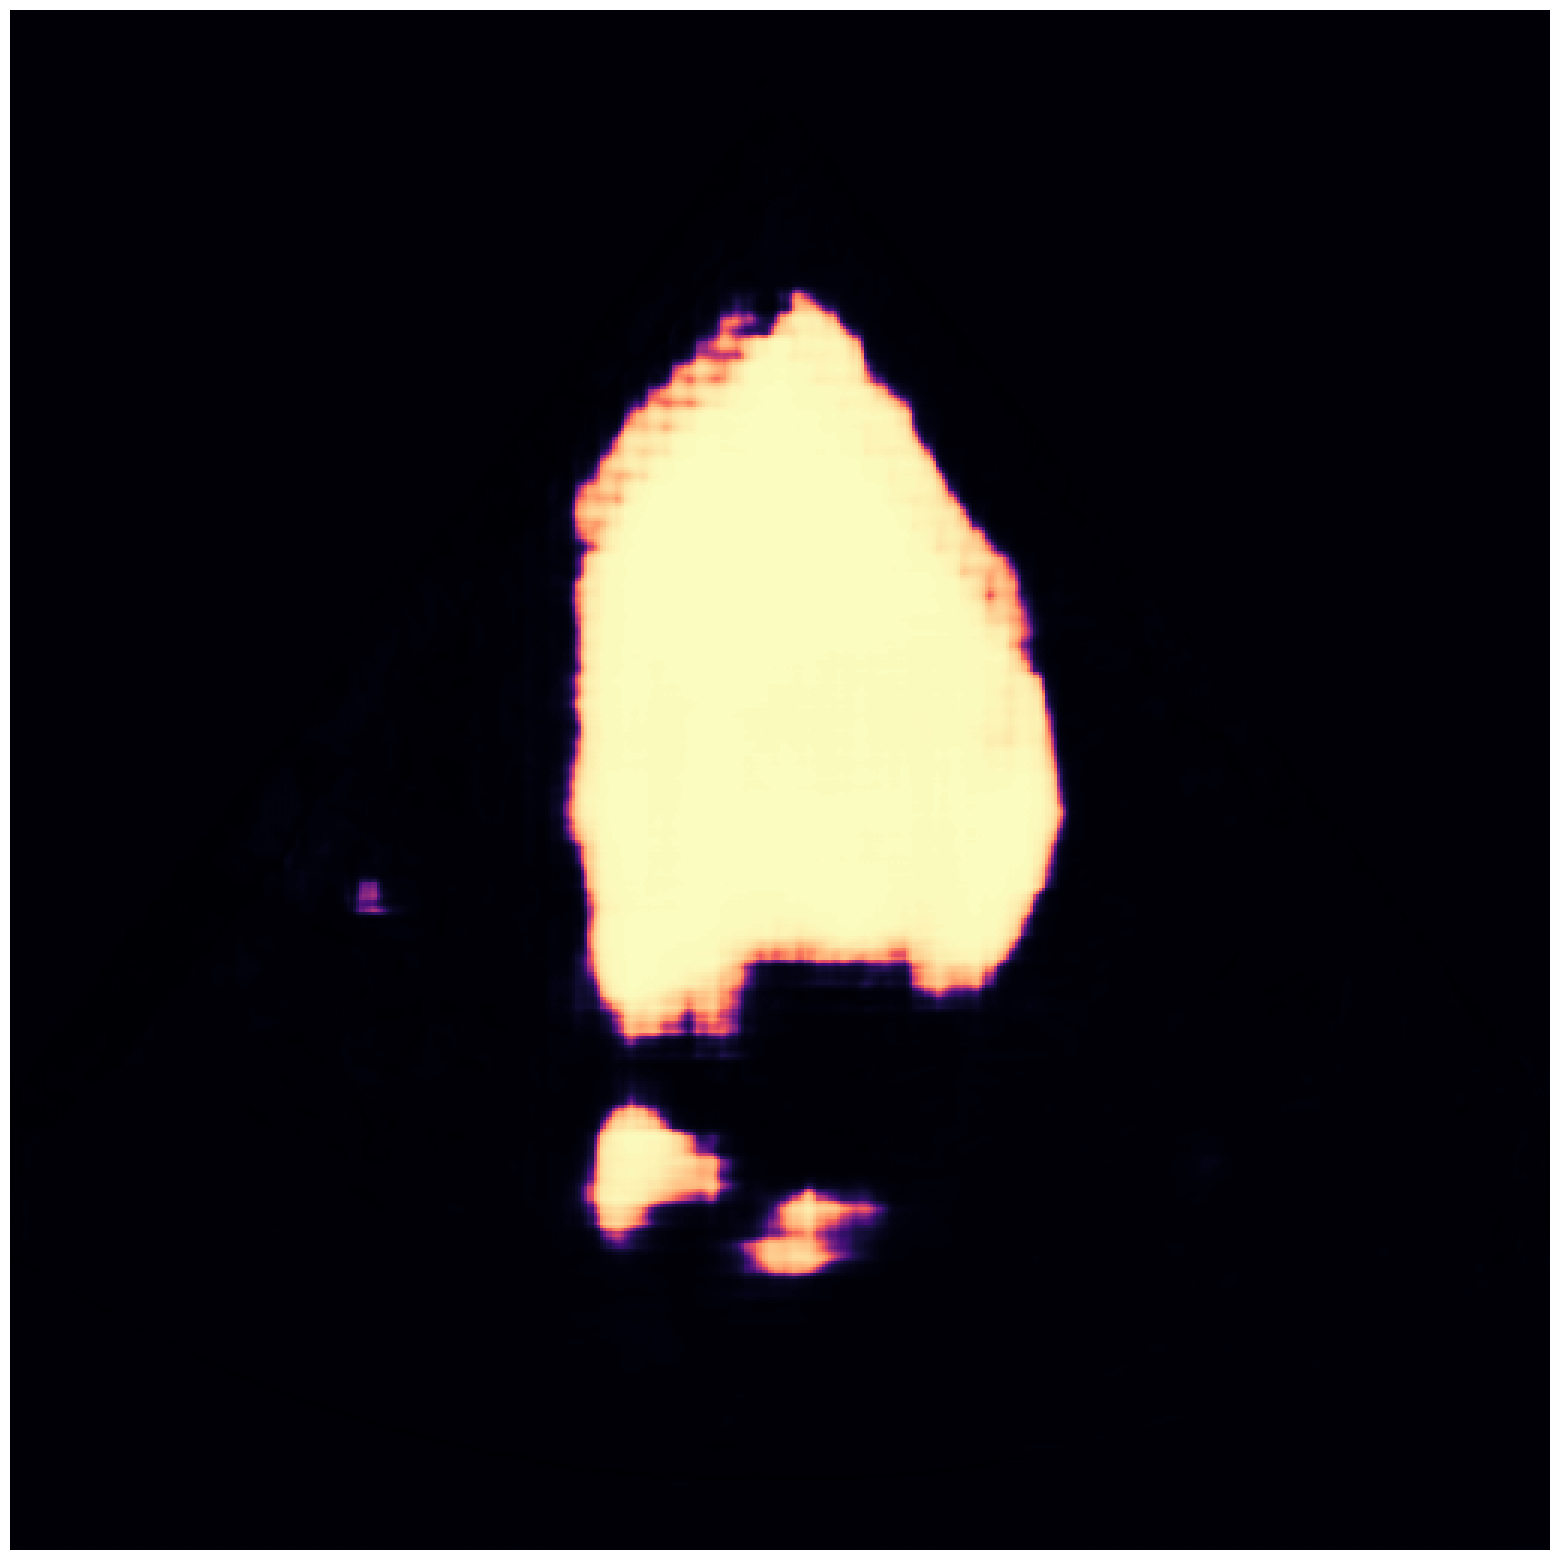

MSD-Pancreas |

![]() |

| (a) Original pred. | b) Consema | ——— c) Standard CRC ——— | ——— d) RW-CP (Ours) ——— | |||

Visually, we observe in Fig. 1 that RW-CP is able to produce prediction sets much closer to the ground-truth than standard CRC or Consema. Our approach is even able to remove small over-segmentated areas, whereas methods such as Consema can only increase the size of the prediction set, even when the segmentation model produced false positives.

We hypothesize that the performance of RW-CP stems from its pre-processing step on probabilities, which mitigates the overconfidence commonly observed in deep learning segmentation models [16]. Their raw softmax probabilities are often skewed towards either 0 or 1 (see Fig. 1.c). This overconfidence compresses the effective range of possible values for the empirical threshold used in Conformal Risk Control, making the final prediction mask extremely sensitive to small fluctuations in . On the contrary, by first applying a diffusion process, the pixel-wise probabilities become more varied and less polarized (as shown in Fig. 1.d). This broadened distribution stabilizes the empirical during calibration, leading to a more robust and tighter prediction set, which translates to better overall segmentation metrics